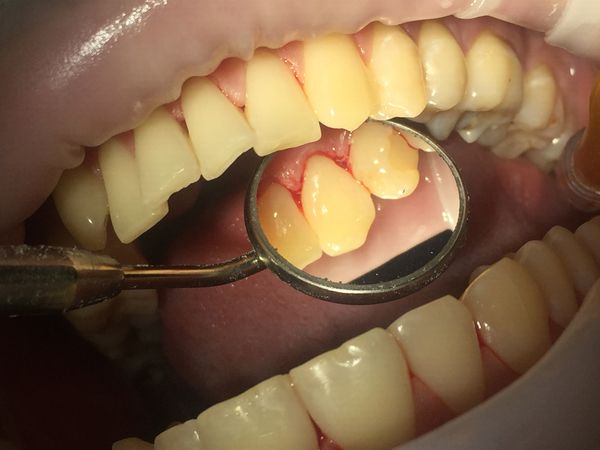

При осмотре полости рта был выявлен мягкий пигментированный зубной налёт на всех зубах верхней и нижней челюсти на язычной и нёбной поверхностях. В области передних зубов с язычной стороны визуализировался твёрдый пигментированный зубной камень. Десна и межзубные сосочки были гиперемированы (т. е. имелось покраснение) и воспалены в области всех зубов.

При осмотре с помощью стоматологического зеркала и зонда был обнаружен твёрдый зубной камень на жевательных зубах верхней и нижней челюсти справа. Непигментированный камень покрывал всю щёчную поверхность жевательных зубов верхней челюсти, при зондировании с трудом откалывался от поверхности зуба. К тому же зубной камень в области жевательных зубов верхней челюсти погружался под десну, тем самым образуя патологический карман между десной и зубом и провоцируя воспаление десны с язычной стороны. При окрашивании зубов специальными индикаторами для выявления зубного налёта был обнаружен непигментированный мягкий зубной налёт на всех зубах с вестибулярной стороны (со стороны щеки и губ).

Гингивит (воспаление дёсен), спровоцированный наличием зубного камня